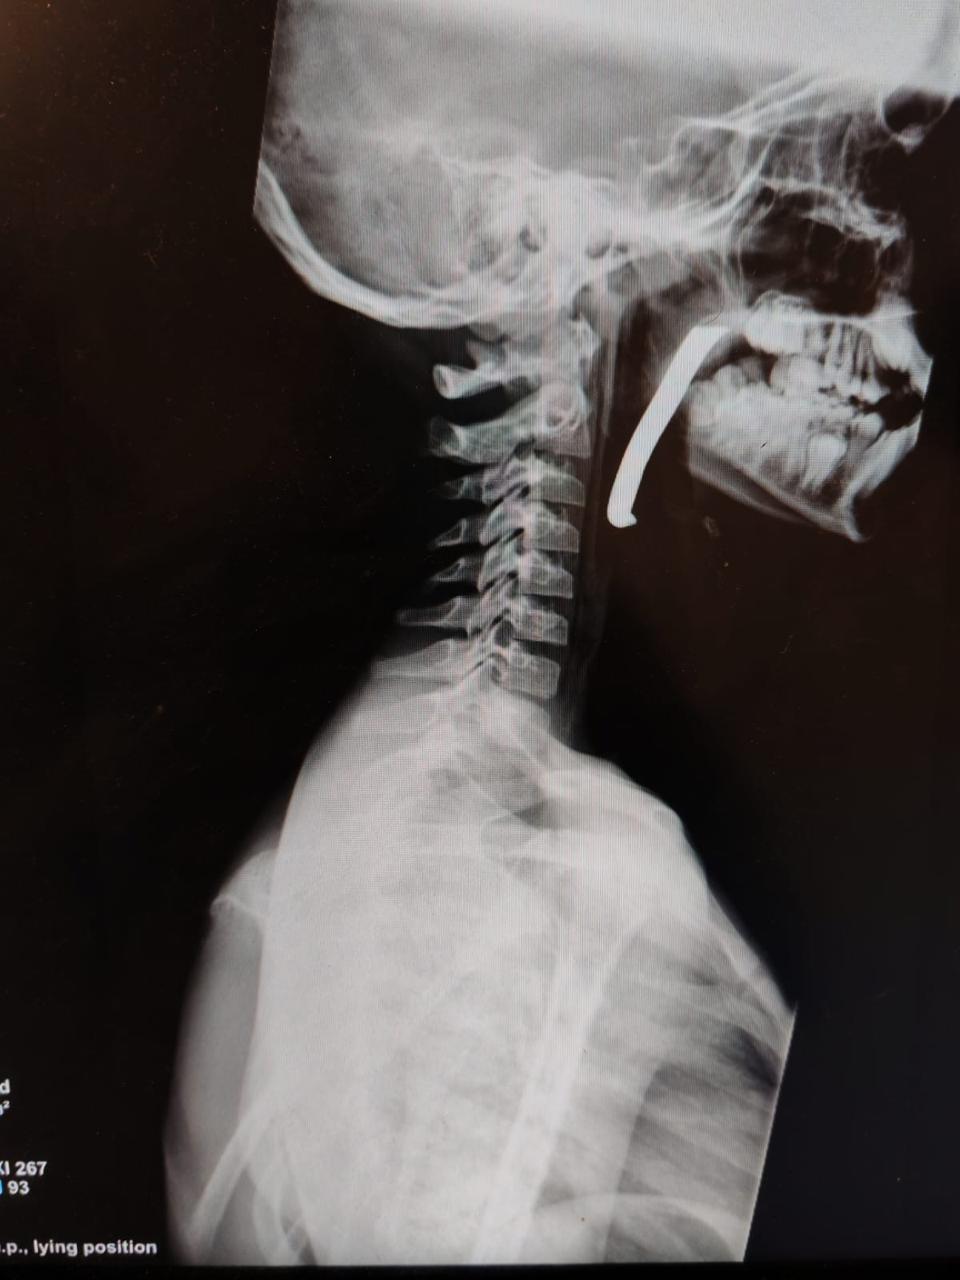

وكالة الناس – أجرت طواقم المستشفى الميداني الأردني جنوب غزة 6، أمس الأحد، عملية جراحية ناجحة لإنقاذ حياة طفل، جرى خلالها استخراج شظية كبيرة الحجم اخترقت الرقبة والبلعوم والمجرى التنفسي، وذلك من خلال استكشاف جراحي دقيق للرقبة.

وأوضح مدير المستشفى، بأن الطفل كان يعاني من إصابة بالغة على مستوى الرقبة والبلعوم، حيث اخترقت الشظية مناطق حيوية وأدت إلى صعوبة في التنفس، مما شكل تهديدا مباشرا لحياته.

وأضاف أن الحالة كانت حرجة، وتطلبت تدخلا جراحيا فوريا نفذه فريق طبي متخصص يضم أطباء في الجراحة العامة، والتخدير والإنعاش، وجراحة الأطفال، وجراحة الأنف والأذن والحنجرة، وبمتابعة دقيقة من الأطباء المختصين، وتم استخراج الشظية بنجاح عن طريق الفم، وحالة الطفل الآن مستقرة.